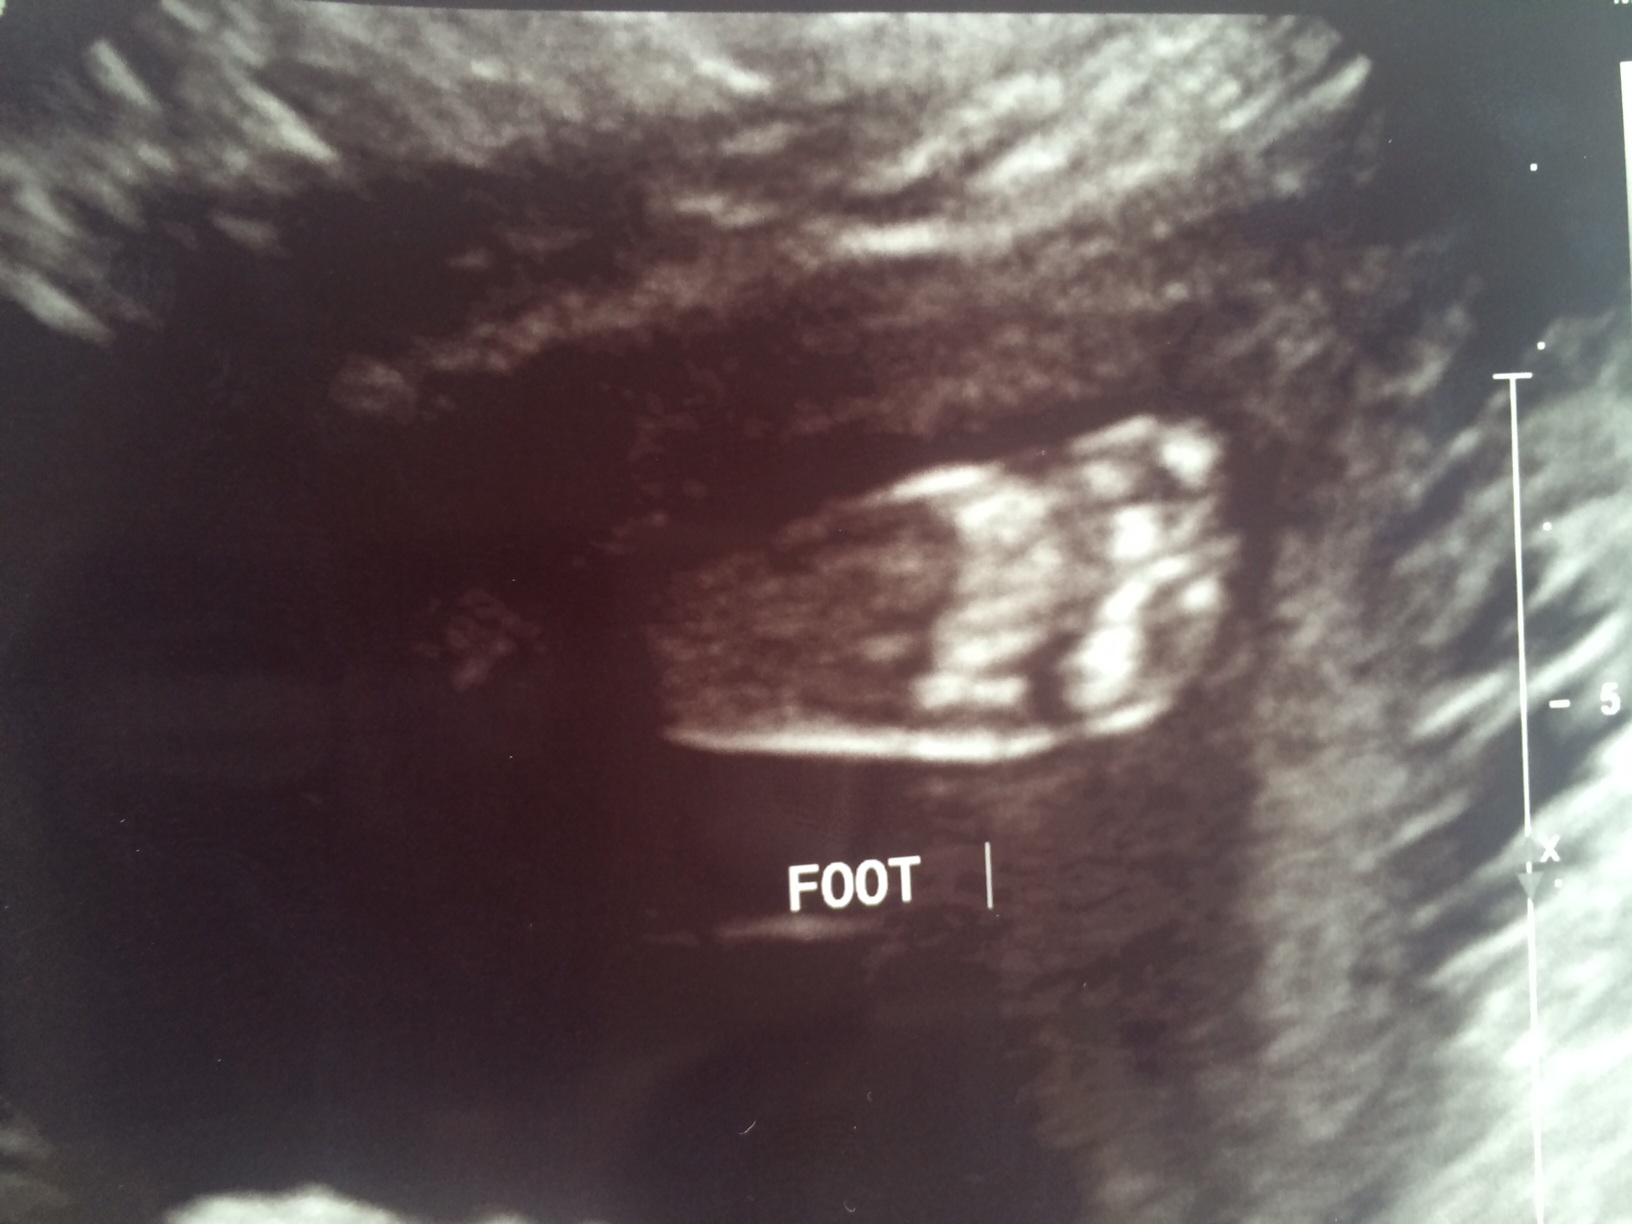

And there’s the foot I can feel poking and fluttering on all sides of my belly button at all hours of the day.

This picture, this sonogram, looks like every other sonogram I’ve every seen really. It’s a little smudge of a baby the size of a mango, but this time the little smudge of a baby the size of a mango is ours.